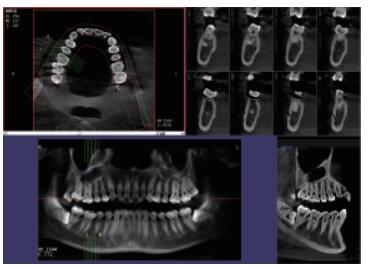

你知道口腔CBCT是什么意思嗎?口腔CBCT是一類特殊的CT,其工作原理是通過X線發(fā)生器以較低的射線量發(fā)射錐形X束,圍繞投照體做環(huán)形數(shù)字式投照,將圍繞投照體多次產(chǎn)生的二維投射影像通過圖像重建算法獲得三維圖像。成像效果更好,有助于醫(yī)生的診斷,對于種植、綜合診斷、正畸等牙科診斷均有較大幫助。

在口腔影像等細(xì)分領(lǐng)域,口腔CBCT的成像質(zhì)量優(yōu)于CT和普放。CBCT的X線利用率更高,且生成的圖像具備很高的各項(xiàng)同性空間分辨率。CBCT技術(shù)優(yōu)勢如下:

三維重建任意斷層

專有三維重建算法,可提供任意位置高清斷層影像。

高清口腔全景影像

通過三維容積影像,提取高清口腔全景影像。

多平面組合重建

可同時(shí)觀察軸向面、冠狀面和矢狀面圖像,方便臨床診斷。